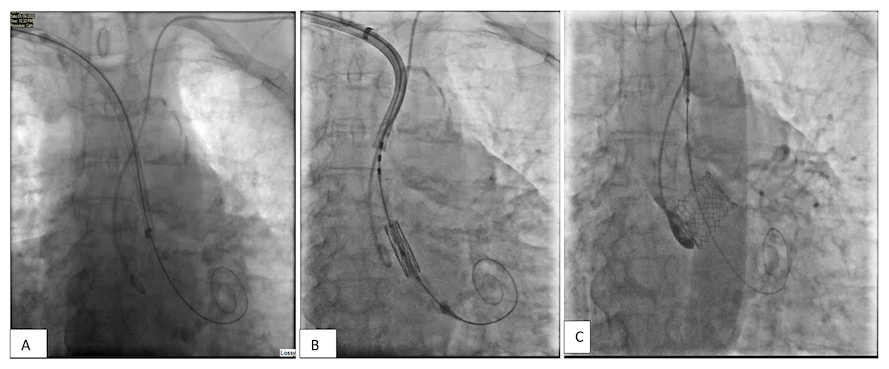

Case 5. An 82-year-old man with severe aortic stenosis and bilateral occluded vertebral arteries was referred for consideration of a TAVI procedure. His TAVI CT showed heavily calcified iliac and femoral arteries. A transcaval approach was excluded due to circumferential distal aortic calcification. He came for the procedure with a creatinine of 310 µmol/L. We placed a Vygon catheter in the right radial and a 5-Fr pigtail in the left radial artery. The right axillary artery was accessed under ultrasound guidance and two ProGlide sutures were placed. A 14-Fr Edwards eSheath was inserted and taken down to ascending aorta positioned just above the aortic annulus. The aortic valve was then crossed, and small Safari wire placed in the left ventricle. A 26-mm S3 Ultra valve was advanced into the sheath which was partially withdrawn to allow space for the balloon catheter/ pusher and valve loading (Figure 5A). We used a significant bend on the pusher to align the valve to the greater curvature of the aorta. As the valve was implanted slowly under rapid pacing, the inner catheter was advanced slightly to hold it just under the annulus (Figure 5B). The angiographic result was very good with excellent valve position and no aortic regurgitation (Figure 5C). Vascular closure was achieved with two ProGlide sutures. The closure was assessed from the right radial approach and confirmed a good seal (Figure 5D). He remained in hospital for 4 days and was discharged home successfully.